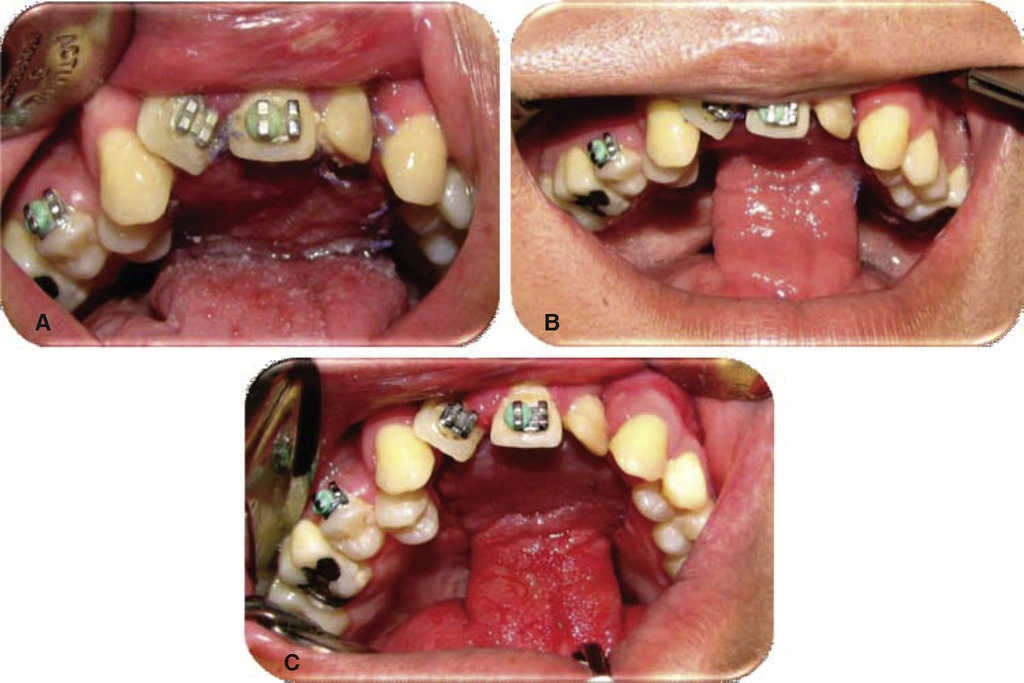

Exploración física. Se observa masculino de 23 años de edad, al examen intraoral se observa secuela de paladar hendido, fístula oronasal de aproximadamente 2.5 × 2.5 cm en región palatina anterior, con comunicación a la cavidad nasal, tejidos circundantes sanos (Figura 1).